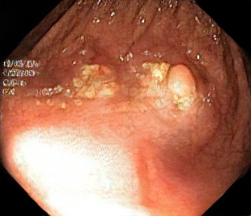

We have used a polyp dataset published with HyperKvasir dataset [51], which consists of polyp findings extracted from endoscopy examinations. HyperKvasir contains polyp images with corresponding segmentation masks annotated by medical experts. We use only this polyp dataset as a case study because of the time and resource-consuming training process of the SinGAN-Seg pipeline. However, the SinGAN-Seg model and pipeline can be used for any segmentation dataset.

A few sample images and the corresponding masks of the polyp dataset in HyperKvasir are shown in Fig 2. The polyp images are RGB images. The masks of the polyp images are single-channel images with white () for true pixels, which represent polyp regions, and black () for false pixels, which represent clean colon or background regions. In this dataset, there are different sizes of polyps. The distribution of polyp sizes as a percentage of the full image size is presented in the histogram plot in Fig 3, and we can observe that there are more relatively small polyps compared to larger polyps. Additionally, a subset of this dataset was used to prove that the performance of segmentation models trained with small datasets can be improved using our SinGAN-Seg pipeline, and the whole dataset was used to show the effect of using SinGAN-Seg generated synthetic images instead of a large dataset which has enough data to train segmentation models. In this regard, this dataset was used for two purposes: